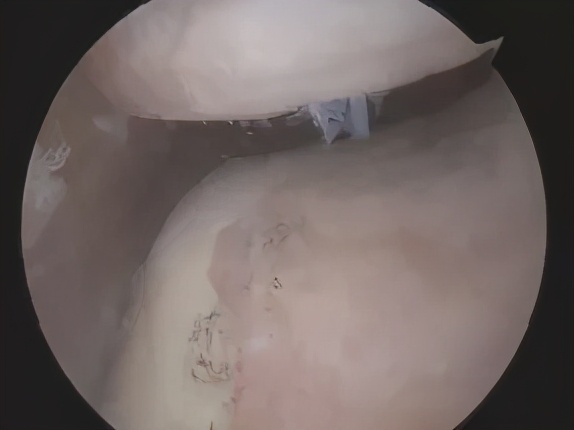

正常的髌股关节

饱经沧桑的髌股关节

内侧半月板损伤